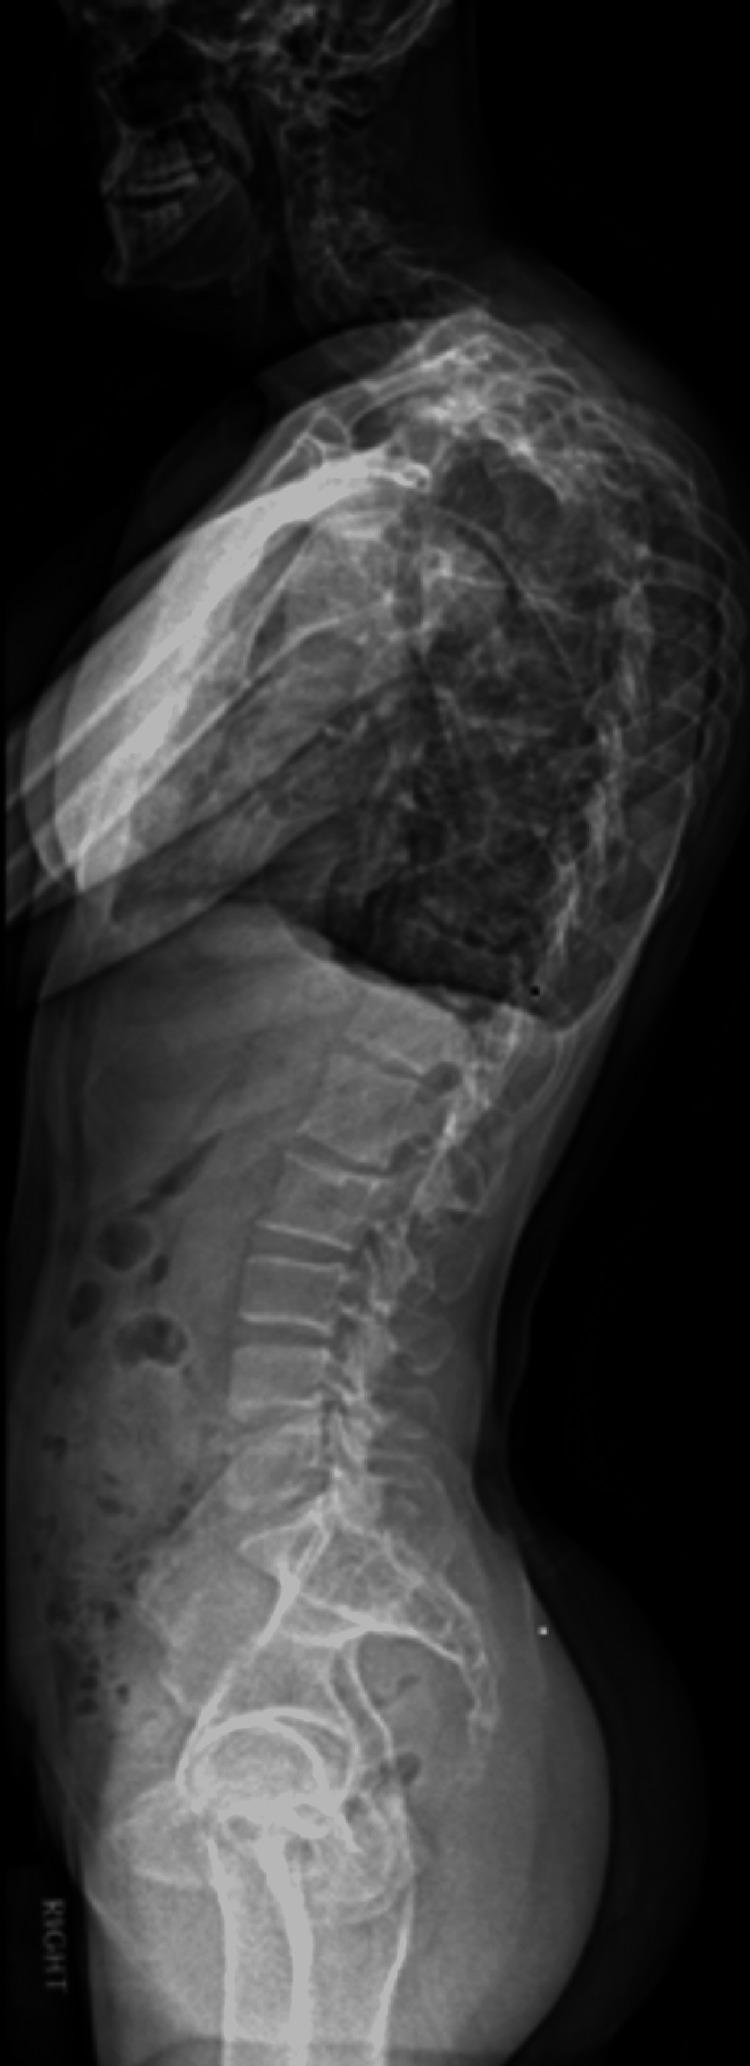

A case of Proteus syndrome with severe spinal canal stenosis, scoliosis, and thoracic deformity associated with tethered cord.

Thoracolumbar scoliosis in a patient with Proteus syndrome: a case report and literature review.